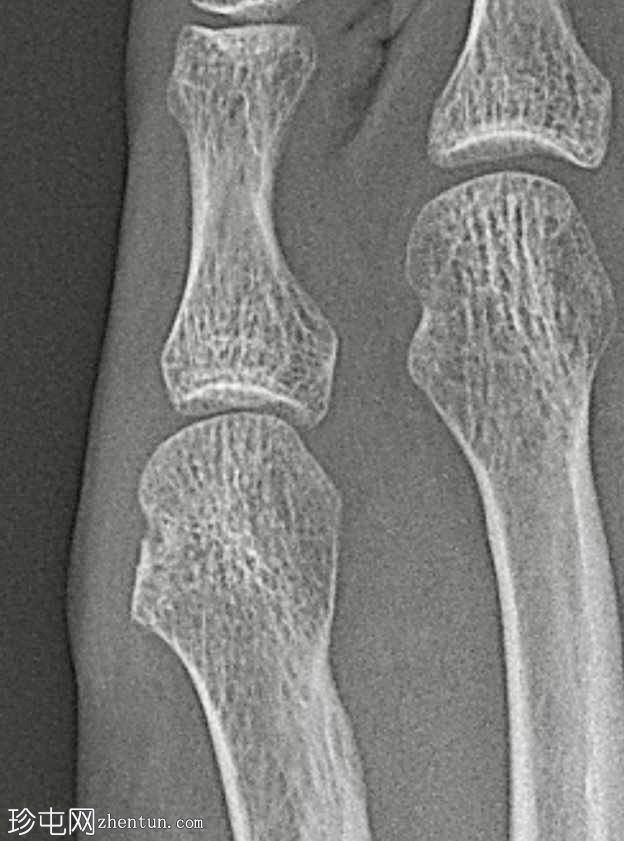

骨质疏松伴皮质变薄

左侧(正位、斜位)和右侧(正位斜位)第五跖骨头关节旁骨侵蚀

边界不清

局部软组织肿胀

斜位X线片、放大倍数和锐化算法对于显示这些侵蚀至关重要